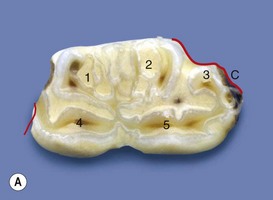

Fig. 8.19

(A) The occlusal surface of a 307 with multiple, branched subdivisions of pulp chambers 1 and 2 caused by dysplastic enamel. The dysplastic enamel has altered the overall shape of the tooth, causing it to poorly fit its alveolus, resulting in some localized periodontal food pocketing and periodontitis (site indicated by superimposed red lines).

(From Dacre et al,26 with permission from The Veterinary Journal.)

image

(B) The mid-tooth section shows all pulp chambers to be empty. The enamel dysplasia has caused reduced dentinal thickness, and the peripheral cementum has become very infolded, appearing like maxillary infundibula, i.e., completely surrounded by enamel. A new cheek teeth pulp horn numbering system is now in use (see Chapter 5).